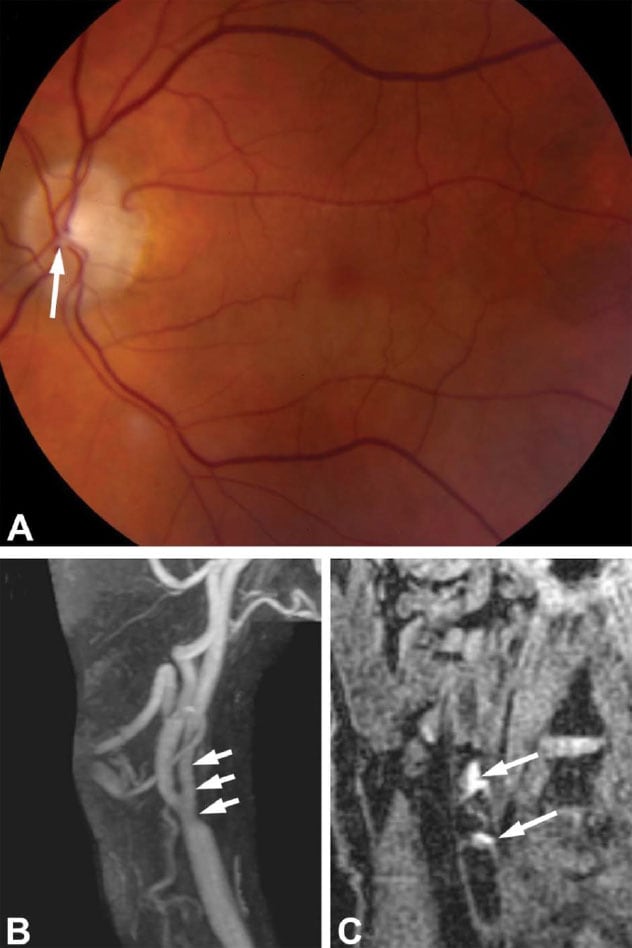

Retinal artery occlusion in the setting of ipsilateral carotid intraplaque hemorrhage with minimal stenosis. An older adult male with a history of coronary artery disease and hypercholesterolemia presented with sudden painless vision loss in the lower left visual field. The patient did not have any other neurological symptoms. A. Fundus photograph demonstrates a plaque in the inferior arcade coming off the disk (arrow) with inferior retinal whitening consistent with a hemiretinal artery occlusion in the left eye. Echocardiography and Holter monitoring did not show any evidence of cardiac structural abnormalities or arrhythmias. B. Magnetic resonance angiography shows long segment irregularity of the left internal carotid artery (arrows) but less than 50% stenosis. C. Magnetization prepared-rapid gradient echo protocol for detection of plaque hemorrhage shows T1 hyperintense plaque of the right carotid bifurcation suggesting intraplaque hemorrhage (arrows). The patient was treated with aspirin and a statin and did not experience any new ocular or neurological symptoms at 23-month follow-up. Image reprinted with permission from Journal of Neuro-Ophthalmology.

"Recently, plaque imaging with various sequences on high-resolution magnetic resonance vessel wall imaging has enabled detection of intraplaque hemorrhage (IPH), which been associated with an acceleration in plaque progression and an increased risk of plaque rupture. Intraplaque hemorrhage has also been shown to be predictive of future cerebral ischemic events," says Muhammad (M. Tariq) T. Bhatti, M.D., a neuro-ophthalmologist at Mayo Clinic in Rochester, Minnesota. "However, whether such an association between carotid IPH and RAO exists remains unknown. If it does exist, it would emphasize the importance of examining for the presence of IPH on high-resolution magnetic resonance angiography (HR-MRA) of the cervical carotid arteries in the setting of acute retinal ischemia."